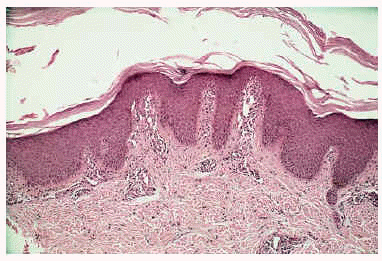

La exploración física puso de manifiesto la presencia de queratodermia palmoplantar de color rosado-amarillento, de bordes precisos y descamación laminar (fig. 1A); fisuras en los pulpejos de los dedos de las manos; placas eritematoescamosas en las rodillas, caras laterales, dorso, zonas aquíleas y maleolares externas de ambos pies (fig. 2A). No se apreciaron lesiones en el cuero cabelludo ni en las uñas ni en las mucosas.

Fig. 1.--A: queratodermia palmar rosada antes del tratamiento. B: tras 2 meses con calcipotriol.

Establecimos, ante la clínica y los hallazgos histopatológicos sugerentes, el diagnóstico de PRP aguda infantil y comenzamos el tratamiento con calcipotriol crema dos veces al día, presentando buena tolerancia y remisión de las lesiones cutáneas tras 2 meses de tratamiento (figs. 1B y 2B). En la actualidad la paciente presenta únicamente hiperpigmentación postinflamatoria en las zonas lesionales, sin ninguna recidiva tras 7 meses de seguimiento.